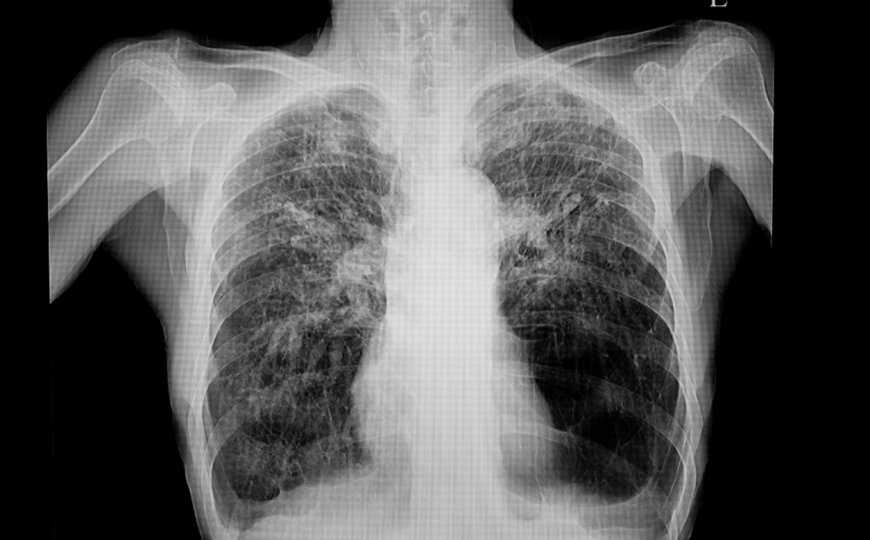

sopone | 123rf.com